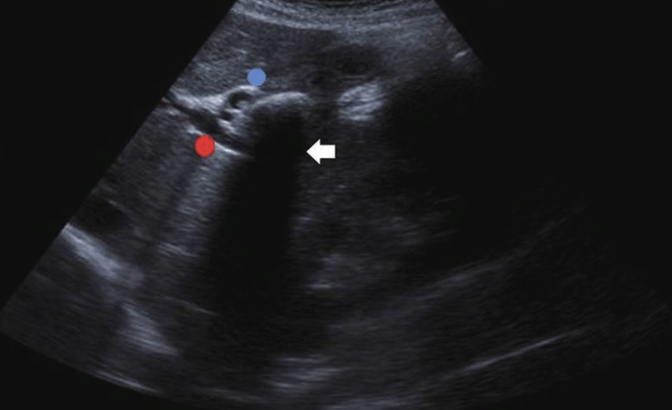

2D US: mixed pattern of echogenicity (hyperechoic from fibrosis to hypoechoic from inflammation), calcifications, normal to atrophic size, nodular surface, dilated/calcified pancreatic duct (> 3 mm), solid mass, thrombosis of splenic and portal vein